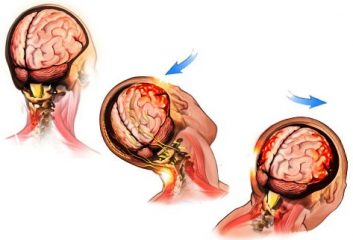

Ως χρόνιο υποσκληρίδιο αιμάτωμα θεωρείται εκείνο που παρατηρείται σε τέσσερις ή και περισσότερες εβδομάδες μετά την κάκωση.

Το 90% παρατηρούνται σε άτομα άνω των 60ετών. Η προηγηθείσα κάκωση αρκετές φορές είναι πολύ μικρή και δεν τη θυμάται ο ασθενής.

Στους προδιαθεσικούς παράγοντες

περιλαμβάνονται, η εγκεφαλική ατροφία, ο αλκοολισμός, η χρήση

αντιπηκτικών και οι αραχνοειδείς κύστεις. Μετά από κάποια κάκωση οι

ασθενείς παραπονούνται για κεφαλαλγία, υπνηλία, αδυναμία άνω ή κάτω

άκρου, διαταραχές λόγου.

Η διάγνωση γίνεται με αξονική τομογραφία

εγκεφάλου. Η θεραπεία περιορίζεται στη διάνοιξη μιας κρανιοανάτρησης,

για παροχέτευση του αιματώματος, υπό τοπική ή ήπια αναισθησία (μέθη).

Επί υποτροπής δύναται να χρειαστεί κρανιοτομία για την αφαίρεση της κάψας, η οποία είναι συχνά υπεύθυνη των υποτροπών.